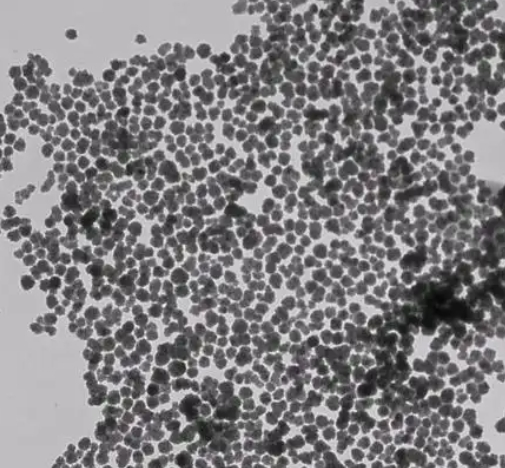

羧甲基壳聚糖修饰的磁性纳米颗粒通过将天然多糖的优异生物功能与磁性材料的可操控性结合,展现出高度的可设计性和广泛的应用潜力。未来,随着生物材料与纳米技术的不断融合,CMC-MNPs有望在精准医学、组织工程、环境治理等多个领域取得突破性应用成果。